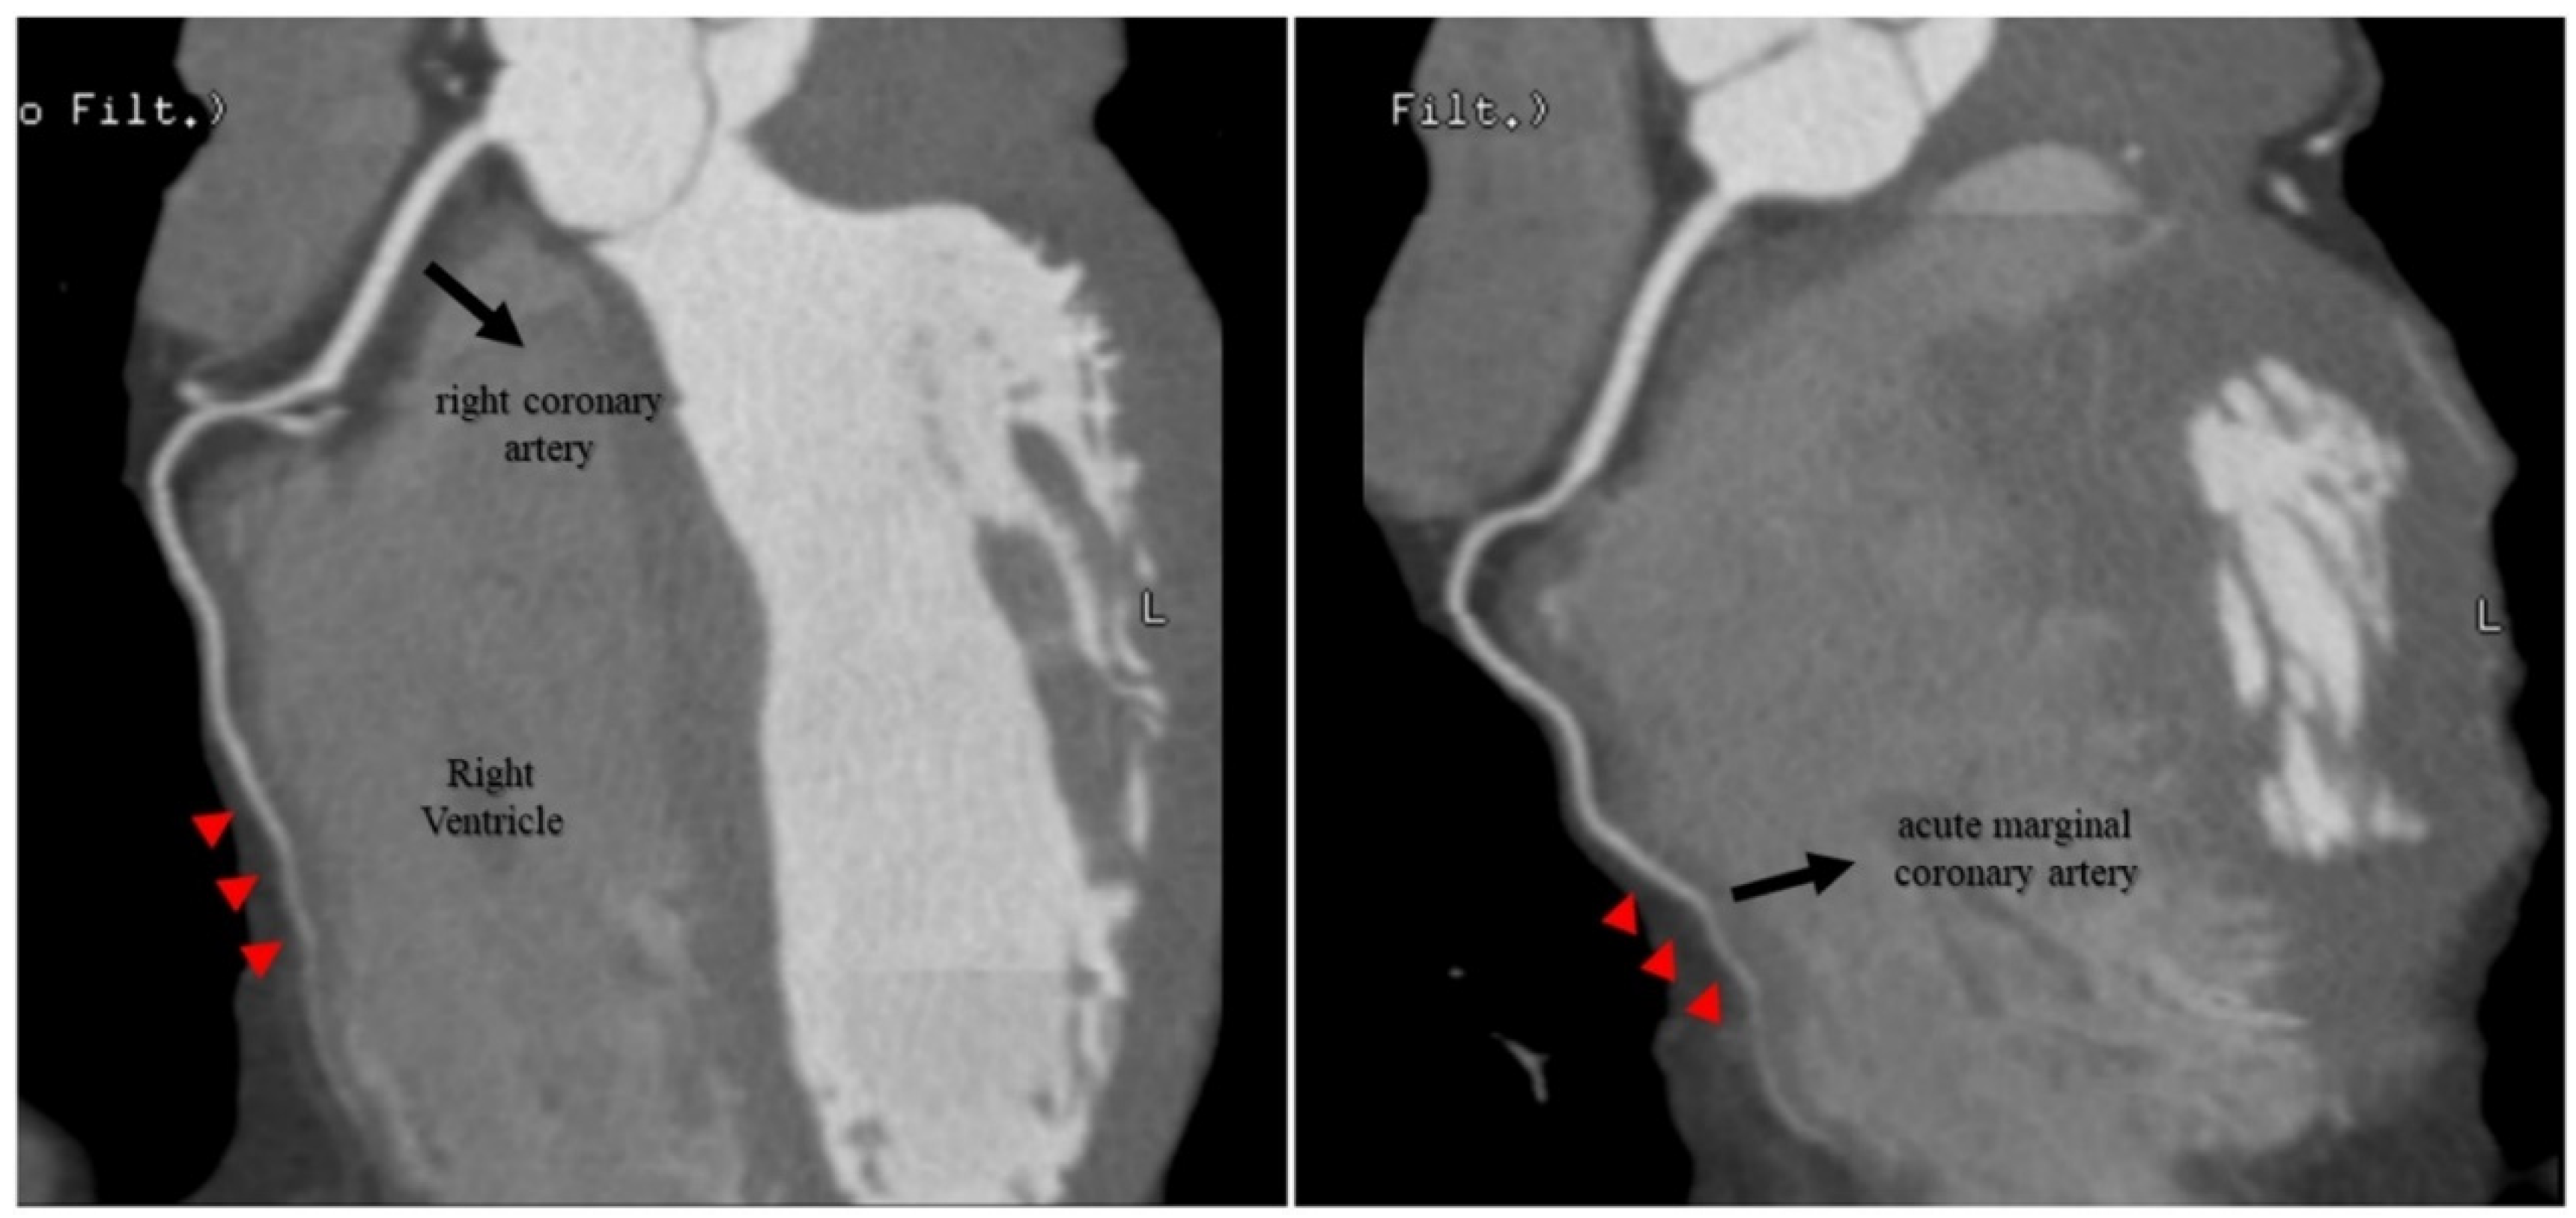

2.4. Investigations